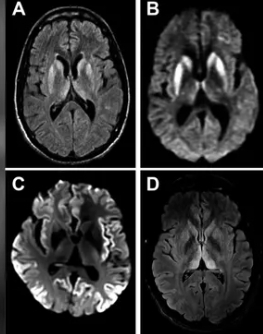

MRI(자기공명영상) 검사 결과 뇌 손상이 발견됐고 추가 검사에서 프리온 단백질 양성으로 밝혀졌다. 프리온은 세포를 둘러싼 세포막에 있으며 세포 통신 및 상호 작용에 관여하는 분자다. 프리온 단백질이 뇌에 쌓이면 주변 단백질이 뒤틀려 신경세포를 손상할 수 있다.

이후 부검 결과 A씨는 변종 프리온에 의해 발생하는 희귀한 질병인 의인성 크로이츠펠트-야콥병(iCJD)을 확진 받았다. iCJD는 뇌에 구멍이 뚫려 뇌 기능을 잃게 되는 퇴행성 신경성 질환으로, 치료법은 없으며 발병하면 반드시 사망하는 치명적인 질환이다.

크로이츠펠트-야콥병 환자의 뇌 MRI 영상. Practical Neurology 캡처